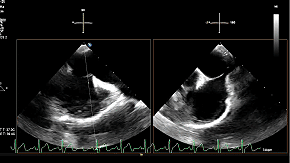

超声心动图(经胸超声心动图,TTE)示:

左心室射血分数(LVEF):75%,左心房前后径:38mm;

二尖瓣P2区大部分瓣叶在收缩期脱入左心房,断裂腱索残端摆动,呈连枷样运动;

连枷宽度:15mm,连枷间隙:6mm;

二尖瓣环AP径:33mm;

AL-PM径:35mm;

有效反流口面积(EROA):0.67cm²。

超声心动图诊断:

二尖瓣反流(退行性,CarpentierⅡ型,4+);

二尖瓣后叶脱垂伴腱索断裂。

术前超声影像

3D

3D彩

术前超声